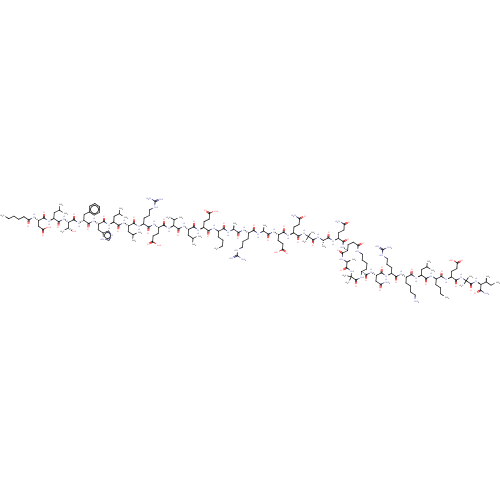

TargetCorticotropin-releasing factor receptor 1(Homo sapiens (Human))

Dupont Pharmaceuticals

Curated by ChEMBL

Dupont Pharmaceuticals

Curated by ChEMBL

Affinity DataEC50: 3.40nMAssay Description:Activity of peptidic agonists on corticotropin releasing factor receptor receptor using agonist-stimulated adenylate cyclase assayMore data for this Ligand-Target Pair